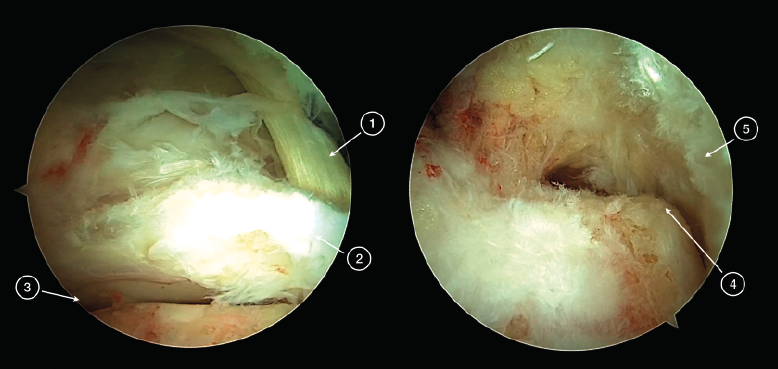

Los portales endoscópicos posteriores de tobillo (posteromedial y posterolateral) se localizan al mismo nivel de la punta del peroné o ligeramente distales a ambos lados del tendón de Aquiles. Se utiliza el portal posterolateral como portal de la visión y el portal posteromedial como portal de trabajo. La técnica endoscópica sigue inicialmente los pasos descritos por Van Dijk(10). La fascia de Rouviere y Canela debe abrirse para acceder a las estructuras de la región posterior del tobillo. Es importante que durante la creación del área de trabajo, la fascia de Rouviere y Canela se abra hacia proximal con el objetivo de evitar la flexión del tendón del FHL cuando este sea transferido hacia el calcáneo. Después de crear un área de trabajo, se identifican las estructuras anatómicas del tobillo a nivel de su región posterior (Figura 1). El tendón del músculo FHL es la principal referencia endoscópica, marcando el límite de seguridad de la zona de trabajo, ya que el paquete neurovascular tibial está situado justo medial al tendón FHL.

Figura 1. Tobillo izquierdo. Visión endoscópica de la región posterior del tobillo (imagen izquierda). 1: tendón del flexor hallucis longus (FHL); 2: proceso posterior del astrágalo (Stieda); 3: articulación subastragalina. Redirigiendo el artroscopio y su visión hacia posterior puede observarse (imagen de la derecha) el tubérculo posterior del calcáneo (4) y la cara anterior del tendón calcáneo (5).

El área de trabajo debe ampliarse hacia posterior para la localización del punto donde se realizará el túnel calcáneo que ubicará el tendón del FHL. Desde la zona de trabajo creada inicialmente, se redirige el artroscopio aún más hacia posterior. El tejido graso de la zona debe desbridarse con un sinoviotomo artroscópico que se desplaza en contacto con el borde superior del calcáneo hasta alcanzar el tubérculo posterior del calcáneo. En ese momento, puede verse la superficie anterior del tendón de Aquiles cerca de su área de inserción.